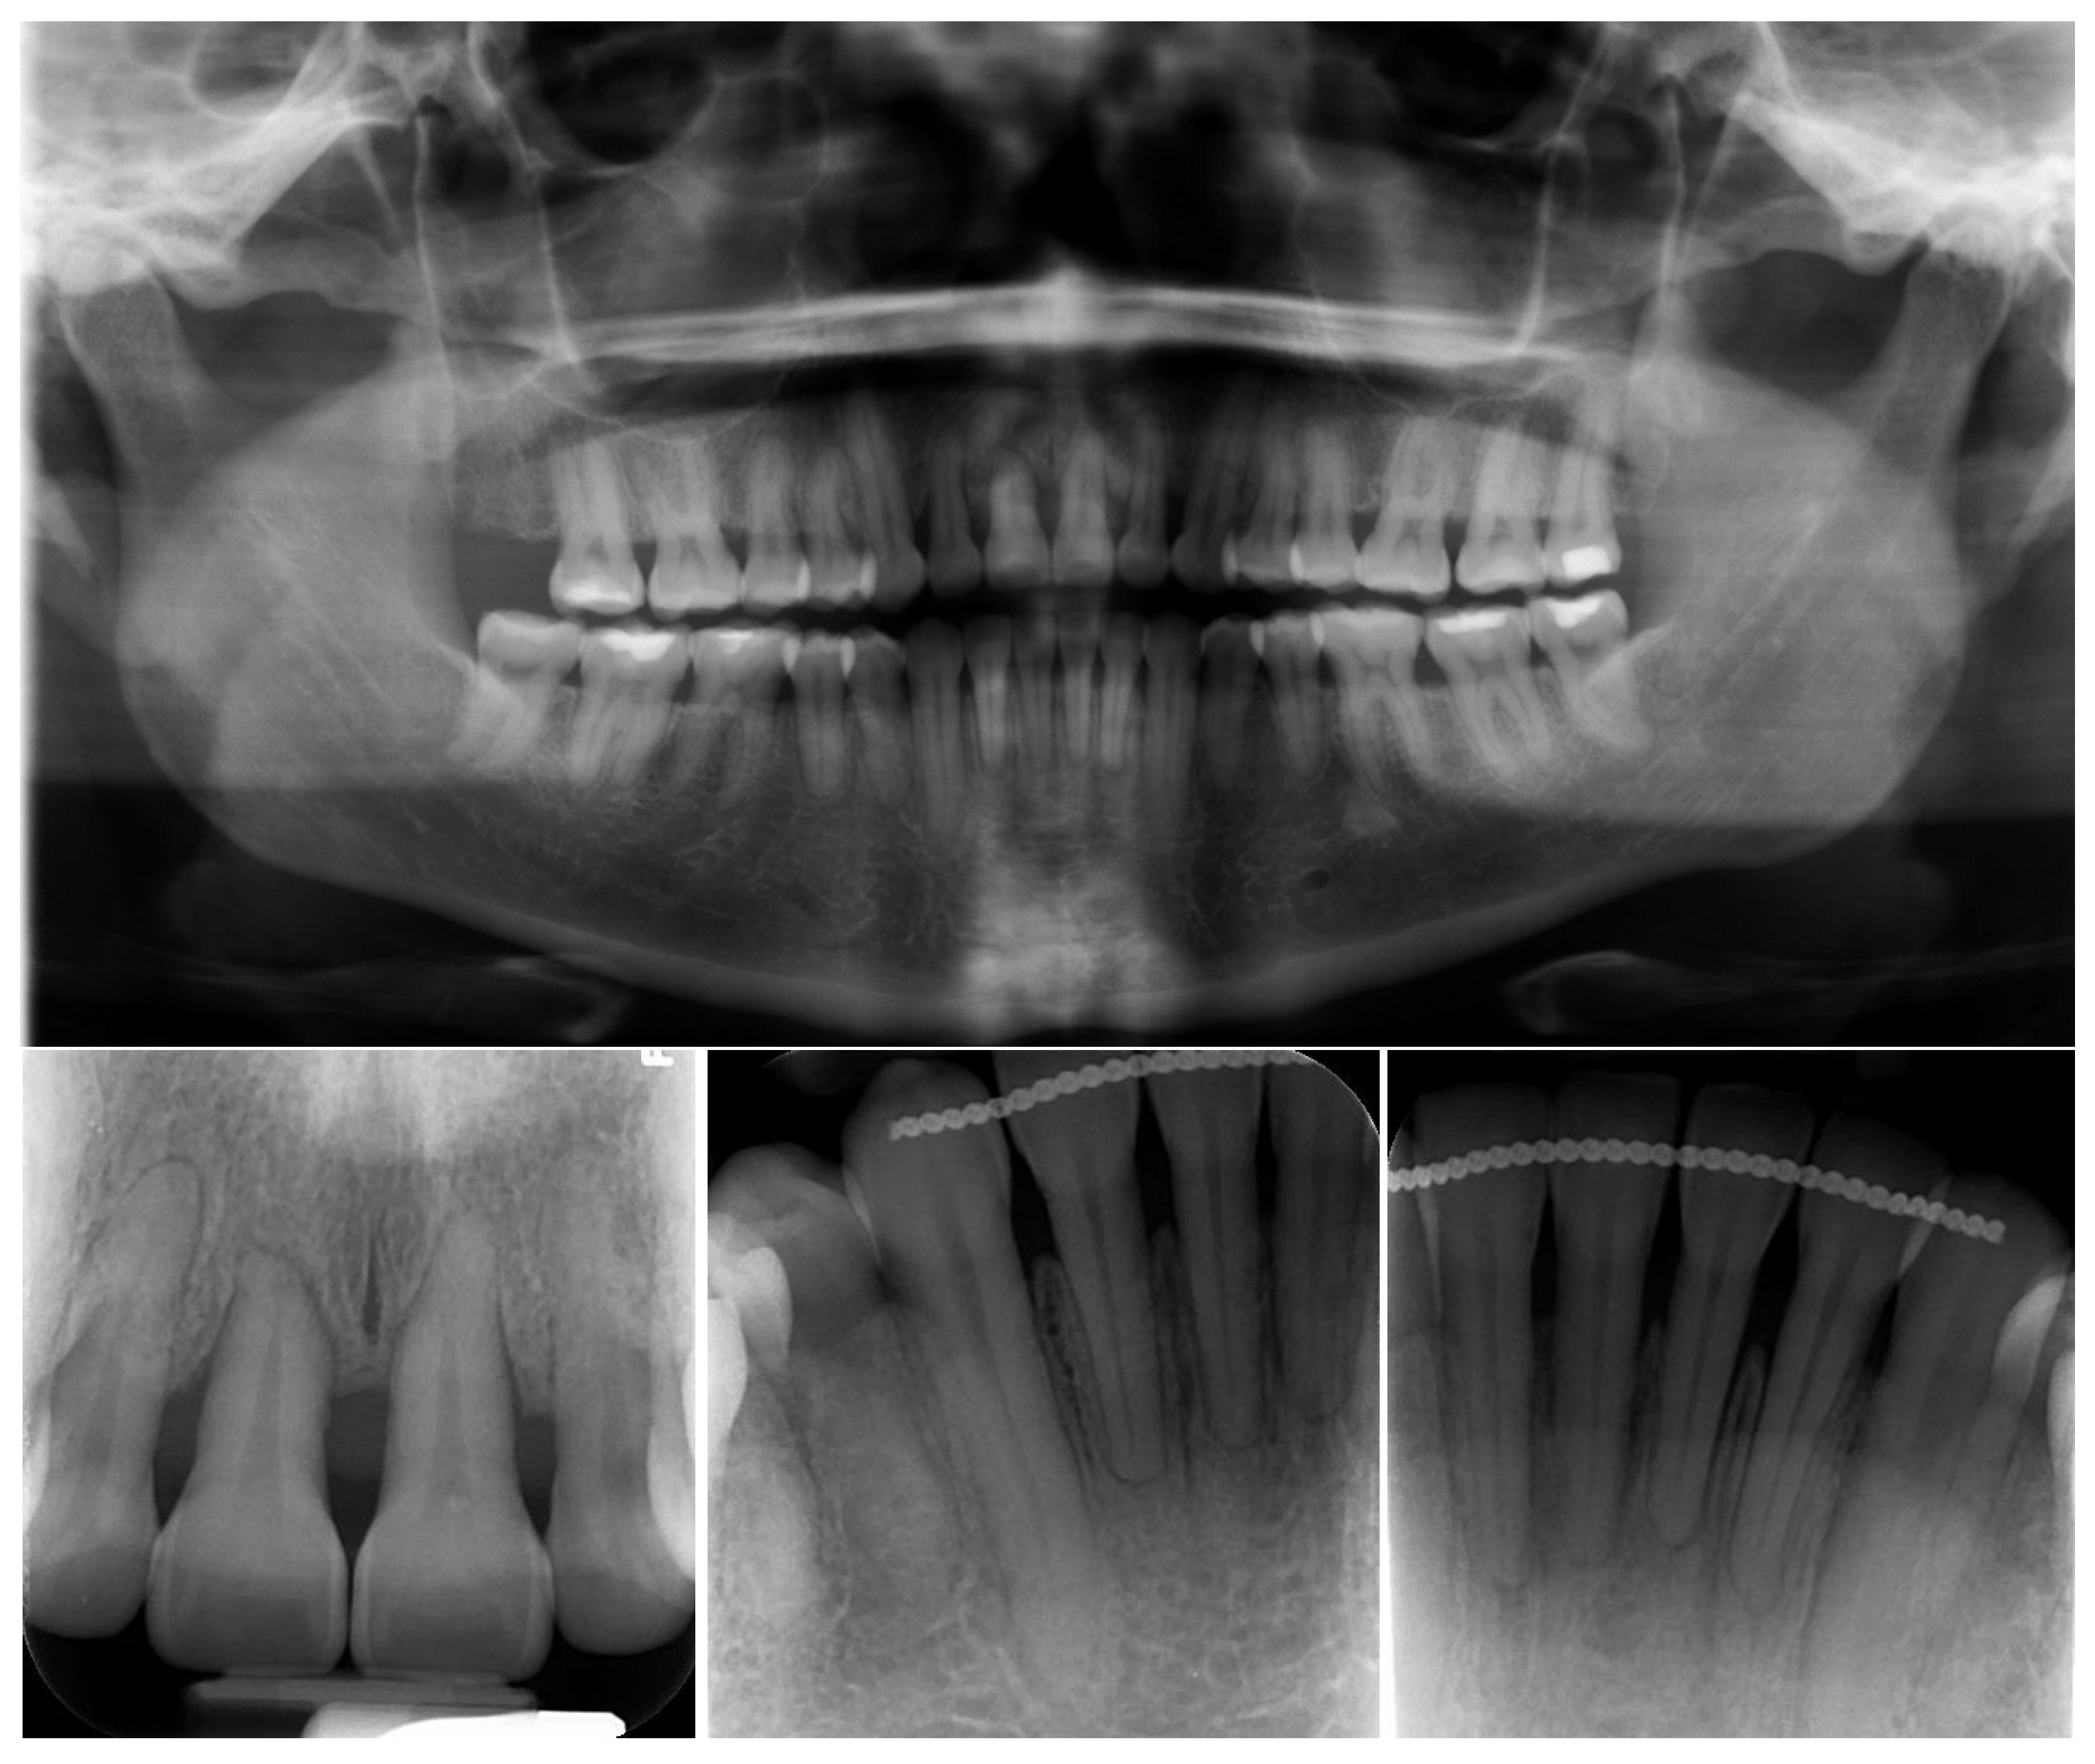

2. Case Presentation

3. Treatment Results